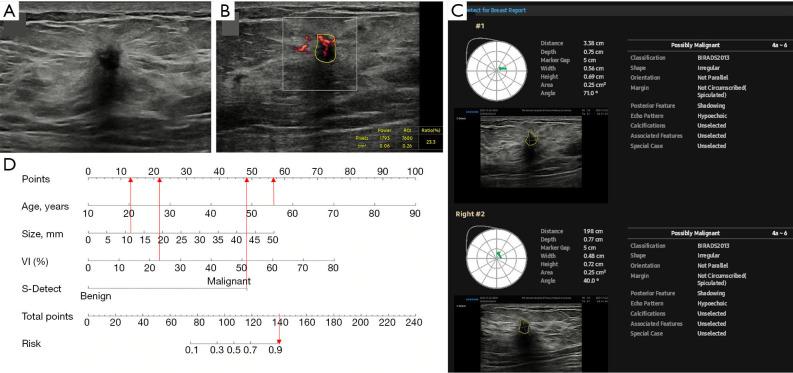

Background: Imaging examination of a breast mass is essential for improving breast cancer detection. Previous screening models of benign and malignant breast masses demonstrated a high level of subjectivity due to the inability to conduct quantitative evaluations. Thus, this study aimed to construct an objective, convenient, and effective nomogram incorporating S-Detect and microvascular flow imaging (MVFI) to predict breast cancer risk.

Methods: Female patients with breast masses detected by conventional ultrasound examinations at the Second Affiliated Hospital of Anhui Medical University between January 2021 and October 2024 were retrospectively analyzed. All patients underwent preoperative assessments with both S-Detect and MVFI. The pathological results served as the gold standard for diagnosis. After screening, a total of 724 breast masses from 712 patients were randomized into the training (506 masses) and validation (218 masses) groups. Univariate analysis assessed patient age, as well as the location, size, vascular index (VI), and S-Detect-based diagnosis of the masses. Risk factors for predicting breast cancer were screened using multivariate analysis. A nomogram prediction model was then constructed. Diagnostic performance, clinical utilization value, and calibration were determined using the receiver operating characteristic (ROC) curve, decision curve analysis (DCA), and calibration curve, respectively. Nomogram risk was calculated for each breast mass for risk stratification.

Results: The training group included 208 benign and 298 malignant masses, while the validation group comprised 85 benign and 133 malignant masses. Multivariate analysis demonstrated that mass size [odds ratio (OR) =1.08; P<0.001], age (OR =1.09; P<0.001), VI (OR =1.07; P<0.001), and S-Detect-based diagnosis (OR =28.37; P<0.001) were risk factors for predicting breast cancer. The area under the curve (AUC) for the nomogram model was significantly greater than that for S-Detect in both the training (0.93 vs. 0.82, P<0.001) and validation (0.91 vs. 0.82, P<0.001) groups. The diagnostic sensitivity and specificity of the nomogram were 93.3% and 79.8% in the training group, and 98.5% and 72.9% in the validation group, respectively. The optimal cut-off value for nomogram risk differentiation between the high-risk and low-risk sets was 0.495, with a significantly higher proportion of malignant breast masses in the high-risk set compared to that in the low-risk set (P<0.001).

Conclusions: This novel nomogram model based on quantitative and objective ultrasound and clinical features can quantify the malignancy risk of breast masses, identify high-risk individuals, and provide a reference for further examinations.